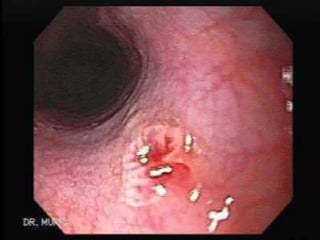

 El papiloma escamoso del esófago

 Es un tumor benigno del epitelio escamoso de baja

prevalencia entre 0.01 al 0.45%,de acuerdo a los

resultados de autopsia y estudios endoscópicos.

Generalmente es asintomático,

 Con predominancia en hombres en una relación de

3:1,

consistente en una lesión elevada, sesil, pequeńa y

redondeada, de superficie lisa o rugosa.

 El papilomaescamoso del esófago  Es un tumor benigno del epitelio escamoso de baja prevalencia entre 0.01 al 0.45%,de acuerdo a los resultados de autopsia y estudios endoscópicos. Generalmente es asintomático,  Con predominancia en hombres en una relación de 3:1, consistente en una lesión elevada, sesil, pequeńa y redondeada, de superficie lisa o rugosa.